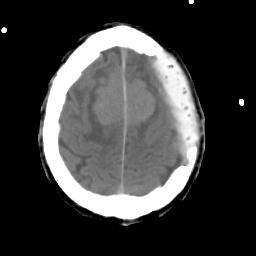

Meningioma: Roentgen-ray CT #2 -- Slice #17

[Home][Help][Clinical] Slice 17